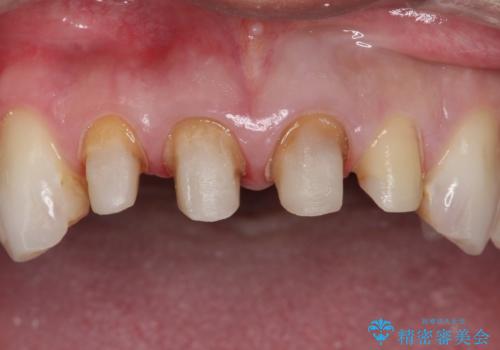

- 前歯のかぶせ物を自然な色味のものにしたいとのことで、来院されました。

保険適用のかぶせ物が装着されており、適合も悪く、変色している状態でした。

土台からの、再治療を行い、オールセラミッククラウンの装着を行う計画としました。